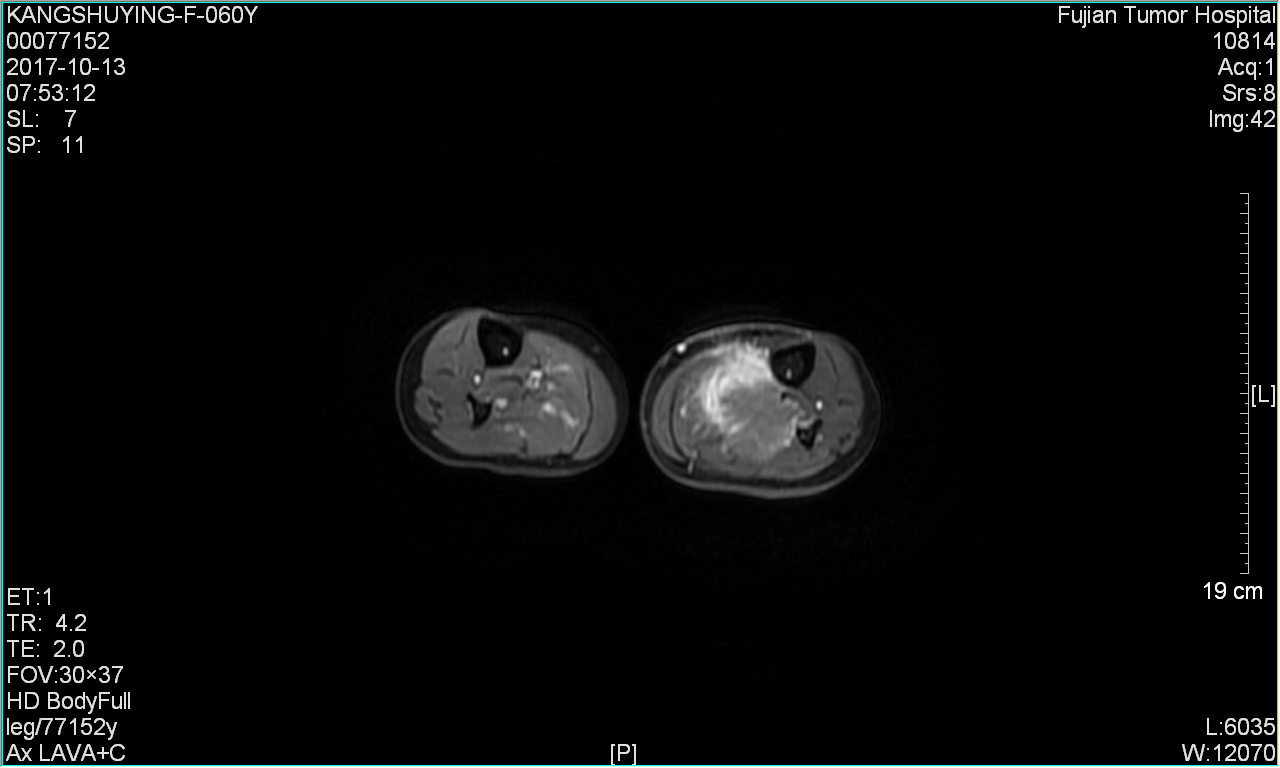

| 影像学检查:(点击查看大图) | 肺CI示:双肺多发大小不一结节,考虑双肺转移瘤。 MRI示:左小腿软组织肉瘤术后,左小腿内后肌群内见不规则软组织肿块,大小约4.5cm*5.4cm*11.5cm;呈T1、T2混杂高低信号,增强后强化明显不均等,边缘不规则,紧贴局部骨膜。 |